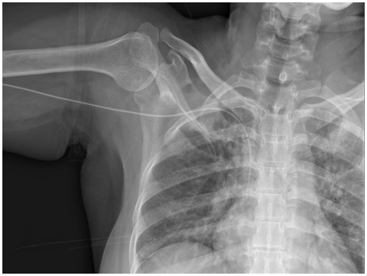

Non-tunnelled CVC are indicated for short term use and these CVC are generally inserted into jugular vein. Non-tunnelled CVC insertion is generally done as bed side procedure and that too in quick time. But, non-tunnelled CVC have high chance of infection and are dislodged easily. Non-tunnelled CVC are generally done by nephrologists from several sessions of acute and emergency dialysis (Figure 3) (Figure 4).

Figure 4 Non-tunnelled Central Venous Catheter (CVC) with dilator